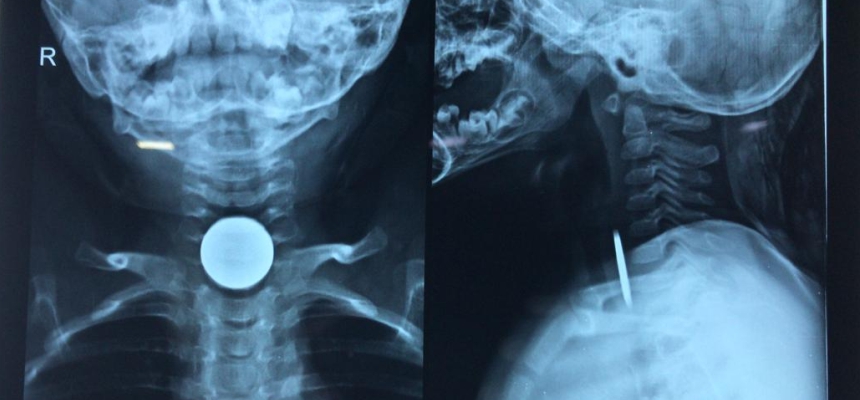

The session covered a range of topics, including the use of regenerative procedures, such as platelet-rich plasma (PRP) and super concentrated cell injections, for the treatment of joint pain, tendinopathy, and other musculoskeletal conditions. Attendees also learned about the role of advanced imaging techniques and lab processing capabilities which help in advancing the treatment effectiveness.

"The field of interventional orthopedics is truly transforming the way we approach musculoskeletal care. By leveraging these non-surgical, image-guided treatment modalities, we can often provide patients with significant pain relief and improved function, while avoiding the risks and extended recovery times associated with traditional surgical interventions," said Dr. Paras Shah, Interventional Orthopedic Expert from USA, now heading efforts at OrthoRenew powered by Regenexx USA.

Preventive Orthopedics is going to change musculoskeletal health. The field of interventional orthopedics is truly transforming the way we approach musculoskeletal care. By leveraging these non-surgical, image-guided treatment modalities, we can often provide patients with significant relief and improved function, while avoiding the risks and extended recovery times associated with traditional surgical interventions.